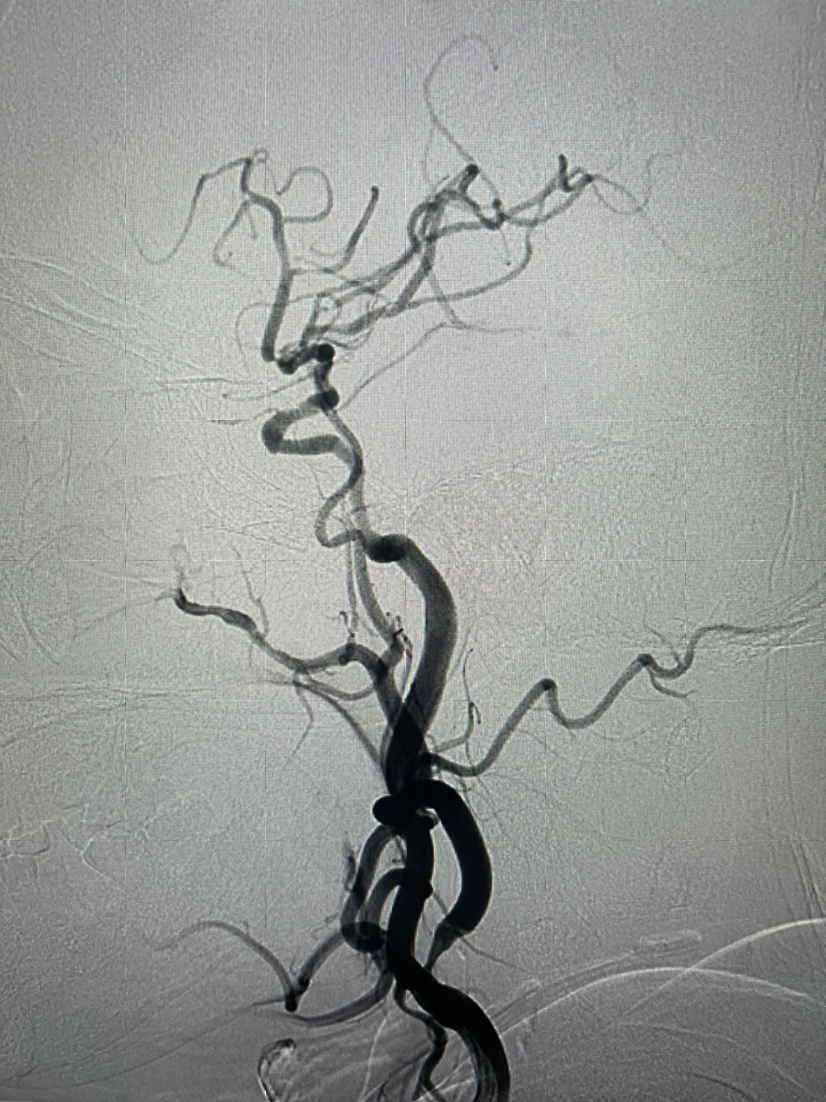

颈内动脉正位造影左侧大脑前动脉缺如

颈内动脉侧位起始部重度狭窄,大脑中M2重度狭窄